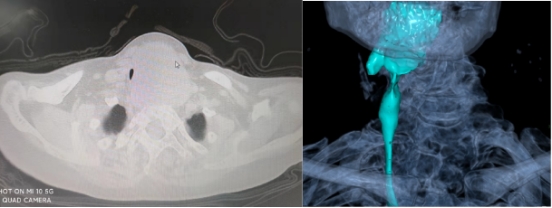

11月14日,患者转入广元市第一人民医院,就诊于肝胆甲乳外科。入院时CT检查发现气道狭窄仅剩1.7mm,气道仅剩一丝缝隙!

入院时CT检查

患者甲状腺巨大肿物致气道重度右移,狭窄气道仅剩1.7mm,深部位于胸骨后方达主动脉弓表面,对麻醉及手术的要求极为苛刻。加上患者78岁高龄,肺部感染、慢性乙肝病毒性肝炎、高血压三级等基础性疾病多,整个治疗过程无疑是雪上加霜,难上加难。相比上一例患者,该例患者年纪更大、气道狭窄程度更严重、病情更复杂,治疗难度更高,远远超出团队想象。